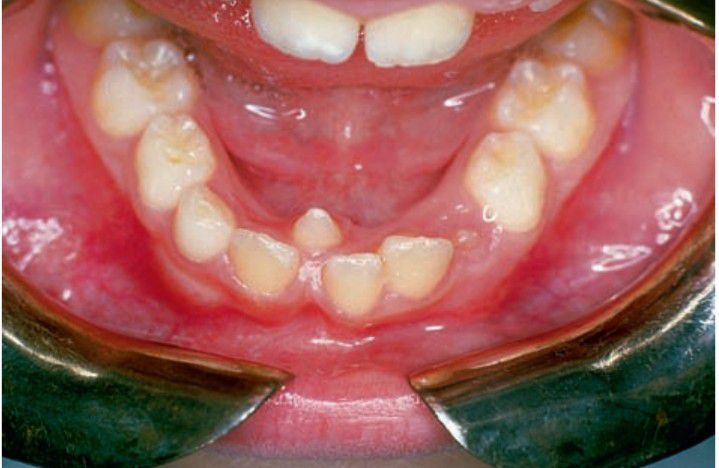

Mesiodens

Extra, or supernumerary, teeth in the dentition most probably result from continued proliferation of the permanent or primary dental lamina to form a third tooth germ